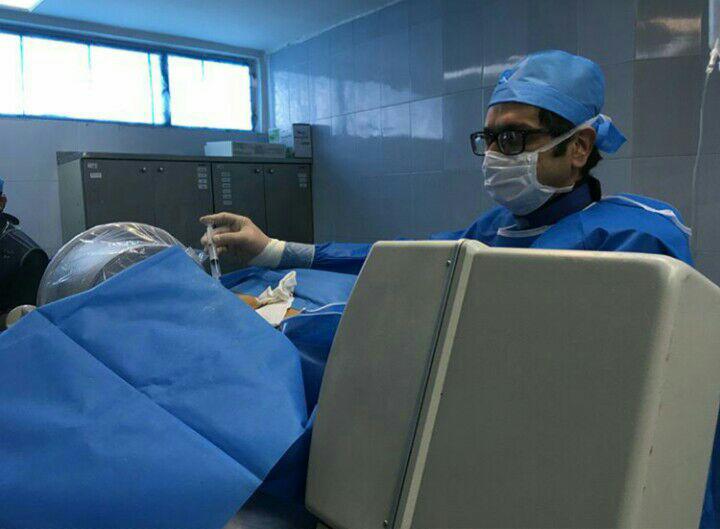

دکتر سعیدرضا انتظاری در تهران

دکتر سعیدرضا انتظاری در تهران

فلوشیپ اینترونشنال درد (فوق تخصص درد)

استادیار دانشگاه علوم پزشکی ایران , عضو انجمن جهانی درد